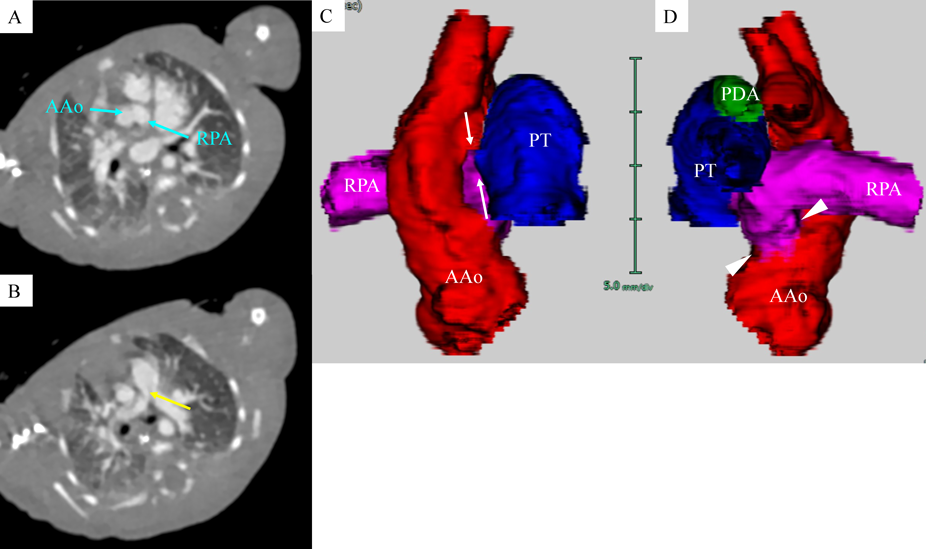

A female baby was delivered by an emergent cesarean section secondary to fetal bradycardia at a gestation of 33 weeks and 4 days. She weighed 1,700 g, and was eventually referred to our hospital at 12 days old. During pregnancy, her mother was doing well without detection of any congenital anomaly including heart disease on routine fetal ultrasonograms. She had no family history regarding congenital heart disease. She was suffering from progressive respiratory distress and congestive heart failure. Levine 2/6 continuous murmur was heard at the left sternal border of the second intercostal space. Her heart rate, respiratory rate and blood pressure were 164 beats/min, 70 breaths/min and 60/30 mmHg, respectively. Oxygen saturation was 99% on room air. Chest X-ray showed cardiomegaly with right pulmonary plethora (Fig. 1). An electrocardiogram showed biatrial overload. Her serum B-type natriuretic peptide level was 3,383 pg/mL. The RPA originated from the left posterior aspect of the proximal AAo. The orifice of the RPA at the proximal AAo was 5.0 mm. Moreover, the RPA was connected to the PT via a 2.0 mm-diameter lumen at the intrapericardial portion adjacent to its aortic origin. She was diagnosed as having AORPA, left aortic arch, patent ductus arteriosus bridging normally between the aortic arch and the PT, and patent fossa ovale by transthoracic echocardiography and computed tomography (Figs. 2, 3). Nitrogen inhalation therapy was started to treat high pulmonary flow.

Fig. 2 Preoperative echocardiogram showed that the RPA arose from the left aspect of the AAo and connected to the PT via a small lumen (white arrow)

AAo, ascending aorta; PT, pulmonary trunk; RPA, right pulmonary artery

Fig. 3 Preoperative computed tomography

Axial views (A, B), and an anterior (C) and a posterior views (D) on three-dimensional computed tomography. The RPA originated from the proximal AAo (A and D, blue arrows and white arrowheads, respectively) and had a connection to the PT just distal to the origin of the RPA (B and C, yellow and white arrows, respectively). The orifice of the RPA at the proximal AAo was much greater than the small channel between the RPA and the PT. AAo, ascending aorta; PDA, patent ductus arteriosus; PT, pulmonary trunk; RPA, right pulmonary artery